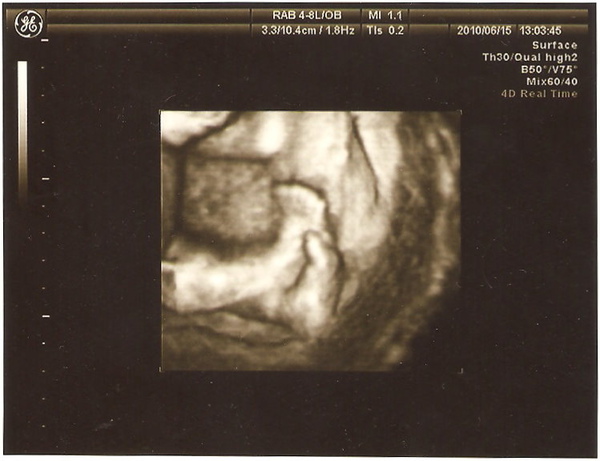

這是耳朵,可是另一邊他壓著,一直照不到

因為每個角度、姿勢都反覆確認,到這裡已經花了十幾分鐘有吧